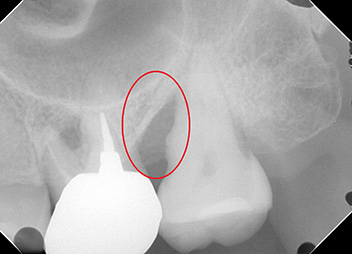

リグロス(歯周組織再生療法)の症例

年齢/性別が表示されたボタンを押すと、下部にスクロールして症例の画像と詳細をご覧になれます。